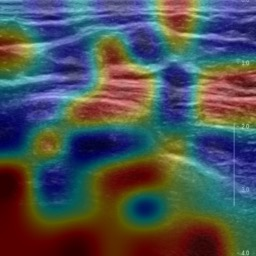

Ultrasonography is an important routine examination for breast cancer diagnosis, due to its non-invasive, radiation-free and low-cost properties. However, it is still not the first-line screening test for breast cancer due to its inherent limitations. It would be a tremendous success if we can precisely diagnose breast cancer by breast ultrasound images (BUS). Many learning-based computer-aided diagnostic methods have been proposed to achieve breast cancer diagnosis/lesion classification. However, most of them require a pre-define ROI and then classify the lesion inside the ROI. Conventional classification backbones, such as VGG16 and ResNet50, can achieve promising classification results with no ROI requirement. But these models lack interpretability, thus restricting their use in clinical practice. In this study, we propose a novel ROI-free model for breast cancer diagnosis in ultrasound images with interpretable feature representations. We leverage the anatomical prior knowledge that malignant and benign tumors have different spatial relationships between different tissue layers, and propose a HoVer-Transformer to formulate this prior knowledge. The proposed HoVer-Trans block extracts the inter- and intra-layer spatial information horizontally and vertically. We conduct and release an open dataset GDPH&GYFYY for breast cancer diagnosis in BUS. The proposed model is evaluated in three datasets by comparing with four CNN-based models and two vision transformer models via a five-fold cross validation. It achieves state-of-the-art classification performance with the best model interpretability.

翻译:超声波分析是乳腺癌诊断的一个重要常规检查,原因是其非侵入性、无辐射和低成本的特性。然而,由于其内在局限性,它仍不是乳腺癌的第一线筛选测试。如果我们能够精确地通过乳房超声图像诊断乳腺癌(BUS),它将是一个巨大的成功。我们提出了许多基于学习的计算机辅助诊断方法,以实现乳腺癌诊断/感官分类。然而,其中多数方法需要事先确定性能模型,然后对ROI内部的跨值进行分类。常规分类支柱,如VGG16和ResNet50等,可以在没有ROI要求的情况下实现有希望的分类结果。但是这些模型缺乏可解释性,从而限制了其在临床实践中的使用。在本研究中,我们提出了一个新的无乳腺癌诊断模型,在超声波图像中进行解释性特征描述。我们利用了先前的解剖学学学知识,即恶性肿瘤和良性肿瘤模型在不同组织层之间有着不同的空间关系,并提议采用状态解析法来编制这一先前的知识。拟议中的HOVer-Trans-Trading-Tradef-trainal Ex-deal-dealal-deal-deal-deal-degraphal-deal-deal-deal-deal-deal-deal disal disal-dal-dal-dal-dal-dal-deal-deal-dal-deal-deal-deal-dal-dal-dal-dal-dal-dal-dal-dal-dal-dal-dal-dal-dal-dal-I-dal-Iversal-dal-Ial-d-d-I-d-d-I-I-I-I-I-I-I-I-I-I-I-I-I-I-I-I-I-I-I-I-I-I-I-I-I-Ial-I-Ial-Ial-I-I-I-I-I-I-I-I-I-I-I-I-I-I-I-I-I-I-I-I-I-I-I-I-I-I-I-I-I-I-I-I-